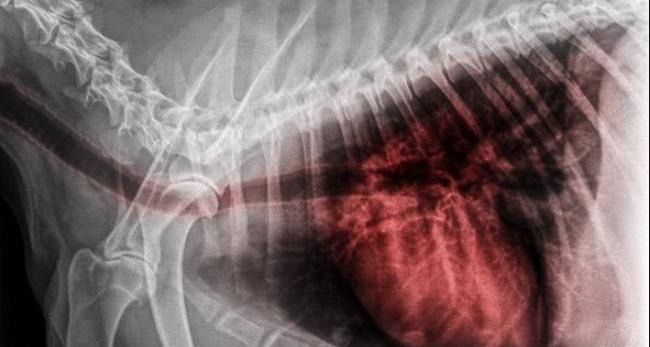

🐶🐱 Doenças respiratórias comuns no outono

Em cães, a tosse seca e repetitiva pode estar associada à traqueobronquite infecciosa, popularmente conhecida como “tosse dos canis”. Já em gatos, espirros frequentes e secreções podem indicar infecções respiratórias virais ou bacterianas.

A identificação precoce dessas condições é fundamental para garantir um tratamento eficaz e evitar complicações.